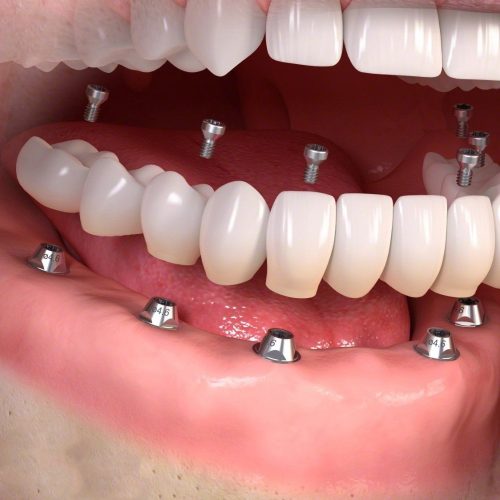

Protocolo Sobre Implante

Temos três tipos de Protocolo sobre implante:

Protocolo convencional que é uma solução para pacientes edêntulos com uma estética, resistência e utilidade muito boas.

Protocolo cerâmico, uma reabilitação de alta resistência para pacientes edêntulos com grande expectativa estética.

Protocolo overdenture que reabilita o paciente para a fala e funções gerais com uma estética mais realista